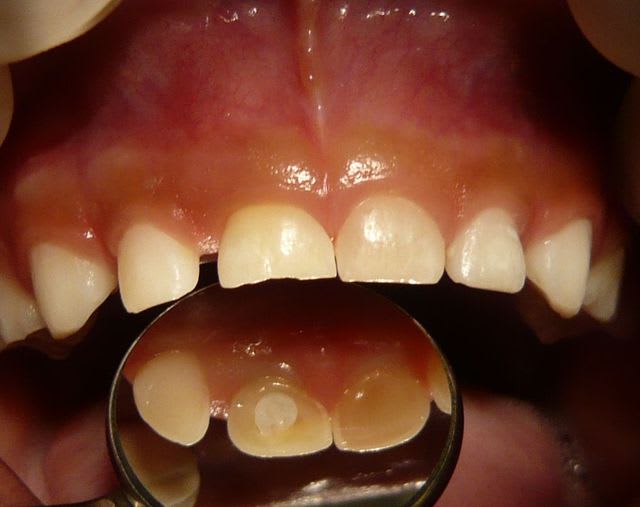

Je réactive ce message avec mon patient vu à 4 mois de la consultation précédente du mois d'aout:

J'avais fait deux séances d'hydroxyde de calcium en août et j'ai obturé sans pression avec un IRM. Il y avait une communication endo-parodontale juste sous le collet en vestibulo distal au départ) visualisée en soufflant légèrement avec la seringue à air.

Voici le résultat en image à 4 mois exactement. Aucune douleur, pas de mobilité dentaire.

Vu que je ne suis pas très objectif sur ce cas clinique (c'est mon fils) et que pour l'instant tout va bien pour lui et que je n'ai pu me résoudre à extraire rapidement la dent (pour l'instant...) comme le conseillait ploc...

Merci de me donner votre avis avec peut être plus d'objectivité... Dois je réintervenir rapidement sur la dent? L'obturation semble étanche.